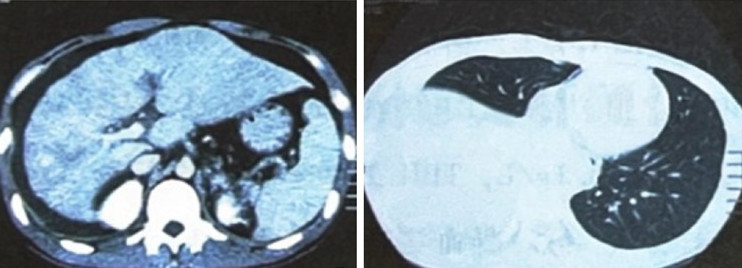

肝、肺CT:肝硬化,食管、胃底

图2 肝脏、肺脏CT